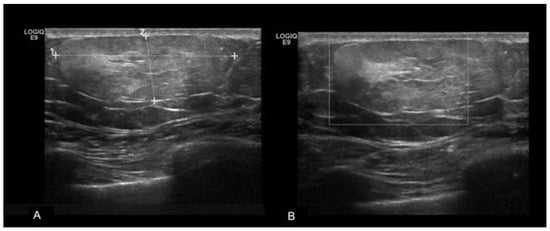

Figure 4.

A 49year-old patient with a history of a blunt trauma on the right breast. In the sub-areolar region (A) of the right breast, there is a hyperechoic mass with anechoic internal components and (B) no signs of vascularization at color-doppler. (C,D) Strain elastography evaluation shows that the mass has an intermediate elasticity. The findings are consistent with fat necrosis.